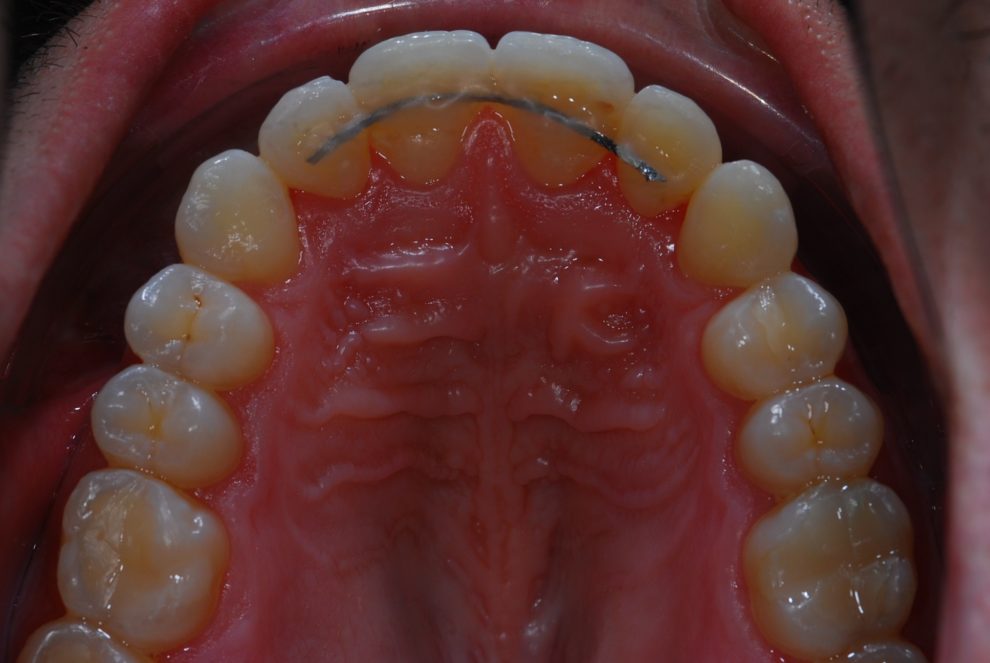

Ortodoncia + Mordida abierta

Nuestro paciente Manuel Vergara Gil acudió a nuestra clínica, y se le hizo una Ortodoncia.